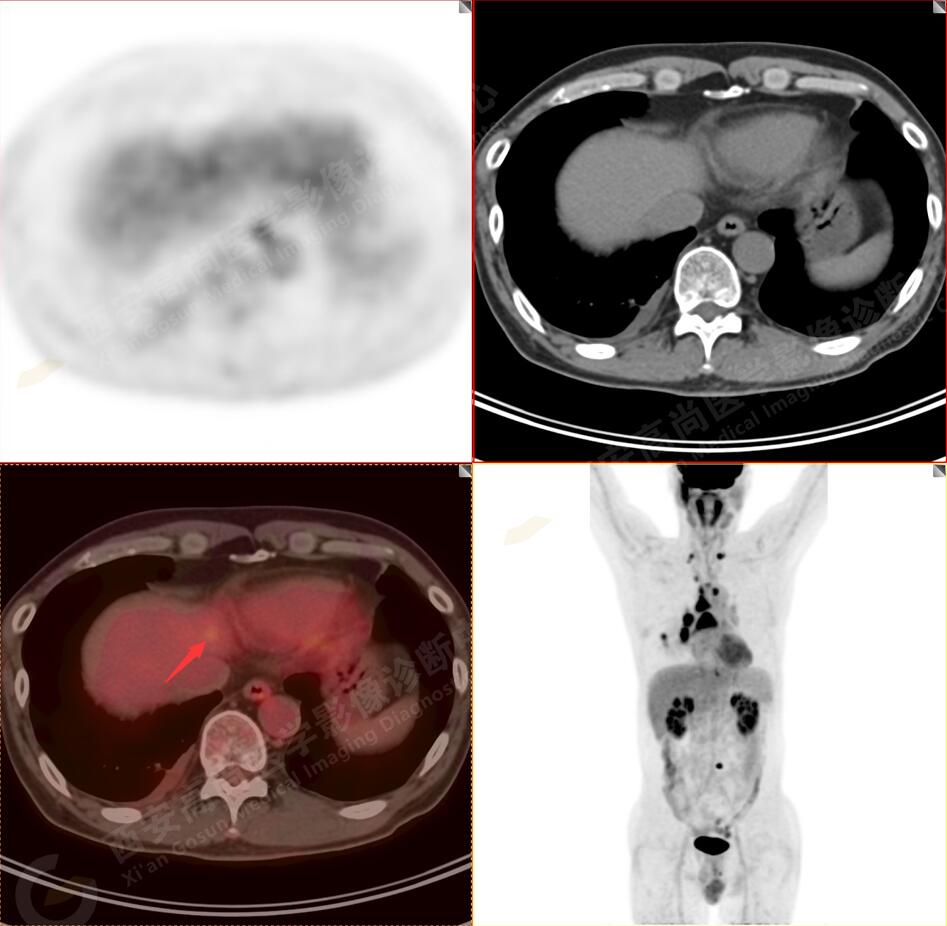

2.以下為全身多發(fā)轉移灶

2.雙肺多發(fā)高密度小結節(jié)灶(最大徑約0.7cm),部分較大結節(jié)呈FDG代謝略增高,均考慮為轉移性病變。

4.右后胸膜輕度增厚,形成多個條狀軟組織病變,呈FDG代謝輕度異常增高,考慮為轉移性病變;右側胸腔微量積液。